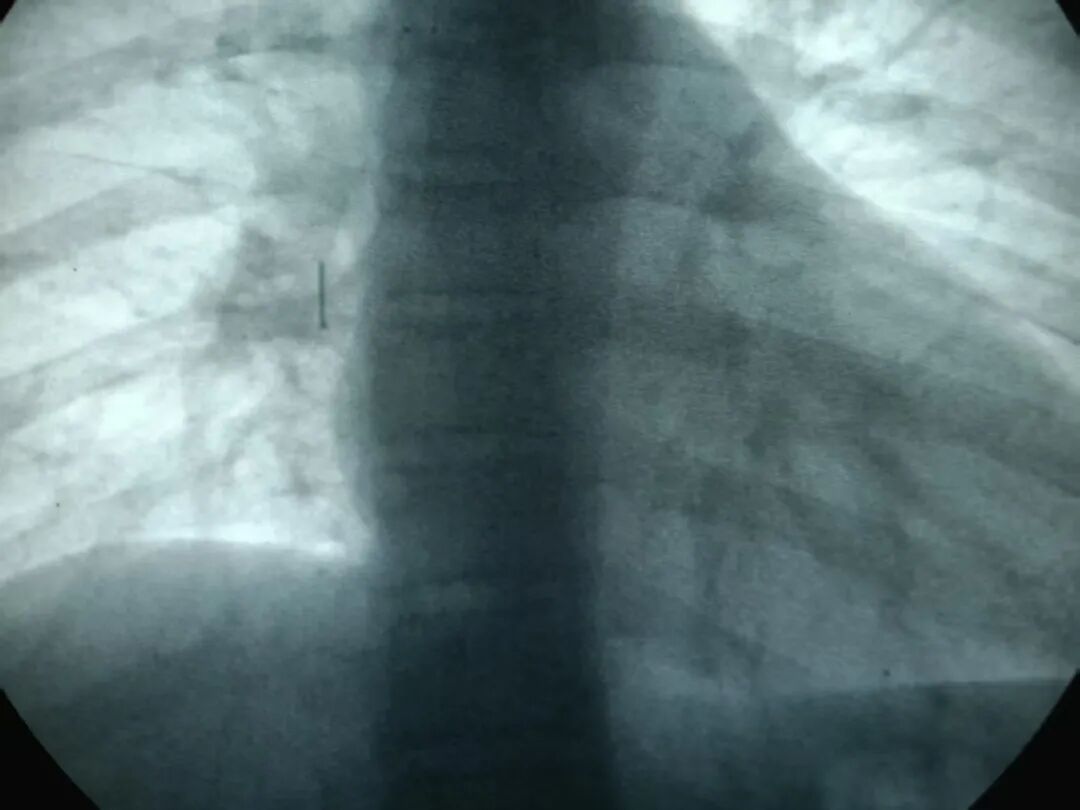

3月13日,家人带他到当地医院做了胸部CT,报告提示“右肺下叶实变影,支气管炎”。医生建议进一步检查,于是他们来到山东大学齐鲁第二医院北院区呼吸与危重症医学科就诊。

呼吸与危重症医学科副主任、呼吸介入亚专科主任王永彬仔细阅片、详细问诊,结合孩子明确的异物吸入史,高度怀疑气管内异物。当天中午,团队立即为小刘进行急症支气管镜检查,因异物为图钉,极易造成气管内大出血,与麻醉科等多科室反复讨论,并进行内镜下推演术中可能遇到的各种问题,并备好各种器材及一旦出现大出血的各种预案。